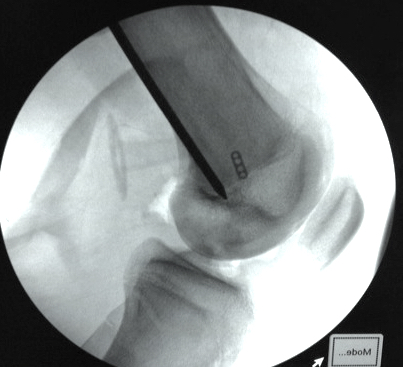

Tibial attachment

- 6 cm from joint line

- just posterior to pes attachment